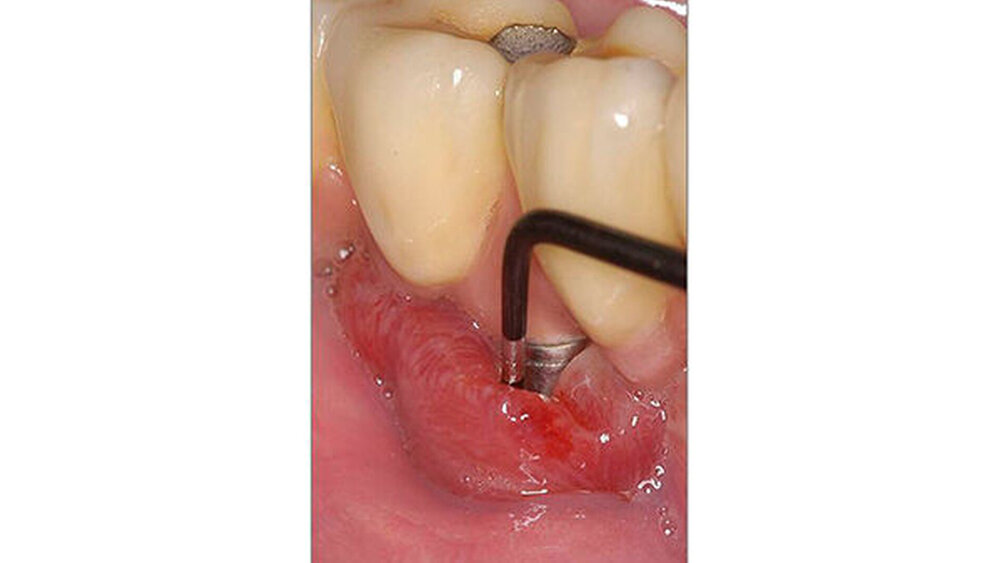

Da Patienten mit Diabetes mellitus ein höheres Risiko für Periimplantitis aufweisen, sollte eine risikoadaptierte Nachsorge nach Implantatinsertion erfolgen.